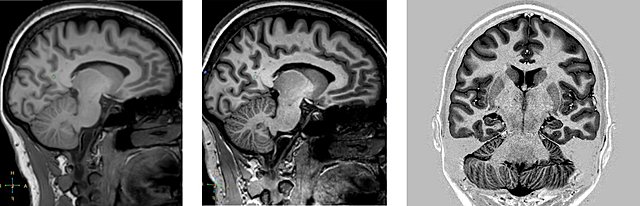

• Resonancia Magnetica

Resonancia Magnetica

Durante esta década se fortalece la investigación con el empleo de imágenes no ya anatómicas sino funcionales, en particular la resonancia magnética funcional y la tomografía por emisión de positrones, que han permitido visualizar la actividad cerebral durante la realización de diferentes tareas cognoscitivas.